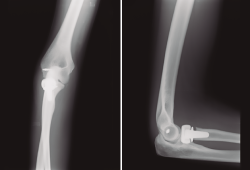

- Fx conminuta de la cabeza de radio Mason IV (no sintetizable), tratada con prótesis de la cabeza de radio ASCENSION® Medcom Tech 22S/cuello corto (Figura 2).

- Fx coronoides conminuta, reinserción con anclaje óseo (Figura 2).

Figura 2. Control radiográfico el 31/10/2017.